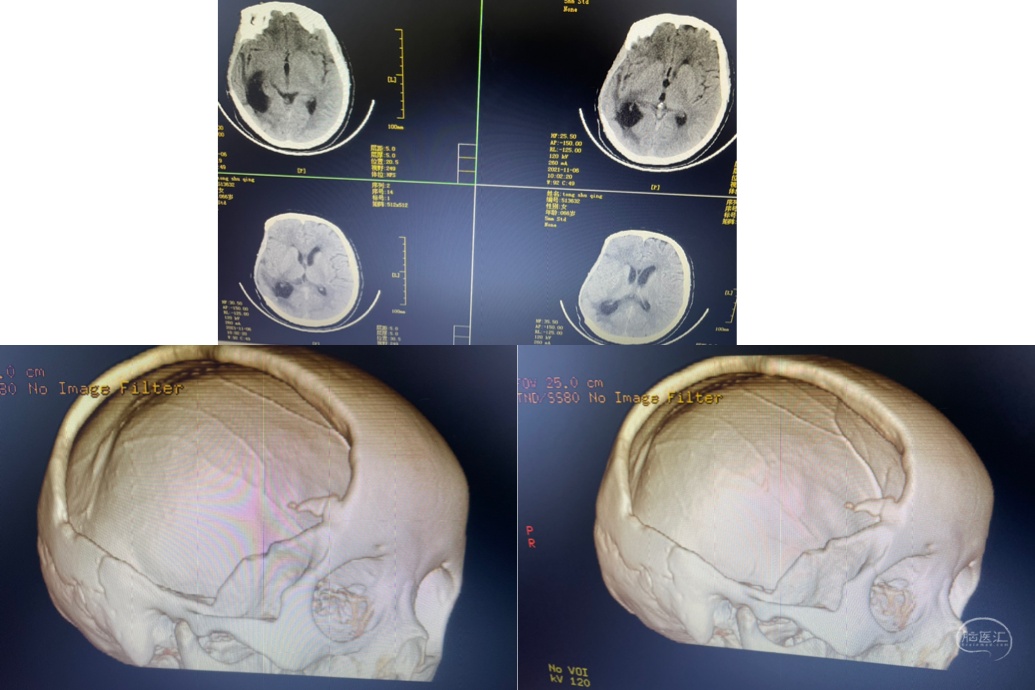

术后半年来院行颅骨缺损修补

钛网颅骨修补

是目前最常用的修补材料